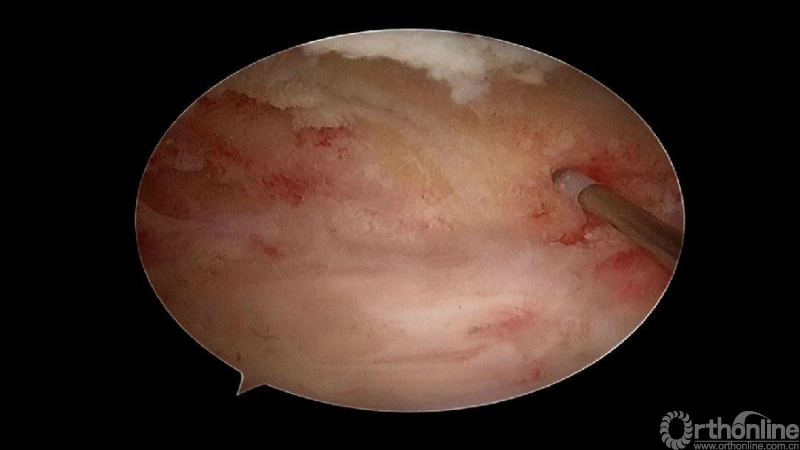

颈椎内镜下单侧入路双侧减压(ULBD)中,减压的难点还是在于识别棘突与椎板的移行部位及对侧结构的显露。

临床上,0°镜子绝对是颈椎UBE的最好用的镜子,但是30°的镜子对侧中线结构的显露及对侧结构的显露具有更广角的视野。在进行同侧减压之前,中线结构的显露是关键。

手术步骤:

1.骨赘位于左侧,选择右侧入路做C4/5椎板切除减压;

2.显露骨赘的内侧面及上下缘;

3.从游离骨块的背侧开始,用磨钻将骨块打薄,然后将骨块的底面与脊髓表面仔细分离,将游离骨块摘除;

4.进一步加深移除骨赘的残余部分,直到显露出对侧的神经根及关节突关节的内壁;

术中操作要点

1. 术中如何确定中线?

2. 术中骨赘的界限?

3. 如何确定对侧结构?

4. 如何确定减压范围?

5. 减压完成后的止血非常重要,高效的止血方法有哪些?